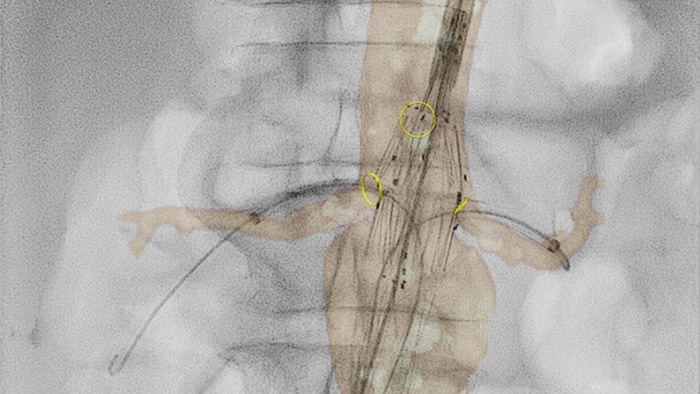

VesselNavigator bietet eine intuitive und fortlaufende 3D Roadmap basierend auf vorhandenen CT-Angiographie- und MRA-Datensätzen, um Sie bei Aorteneingriffen durch das Gefässsystem zu führen. Eine Studie zeigte eine durchschnittliche Einsparung von 170 ml Kontrastmittel während einer endovaskulären Reparatur eines komplexen Aortenaneurysmas unter Verwendung der Bildfusionsführung mittels CT-Angiographie durch VesselNavigator.1 Eine weitere Studie zeigte eine Reduzierung der durchschnittlichen Behandlungszeit von 6,3 (um 1,1) auf 5,2 Stunden bei FEVAR/BEVAR unter Verwendung der Bildfusionsführung mittels CT-Angiographie durch VesselNavigator.2